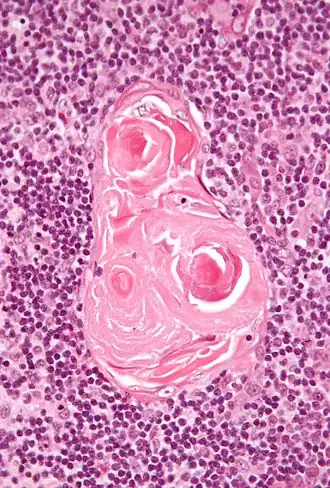

En la porción medular, la red de células reticulares es más gruesa que en la corteza, las células linfoides son relativamente menores en número y son concéntricas, así; son cuerpos con aspecto de nido o madriguera, llamados corpúsculos de Hassall. Estos corpúsculos concéntricos están compuestos de una masa central, que consisten de una o más células granulares y de una cápsula formada por células epiteliales. Son los restos de los tubos epiteliales, que crecen hacia afuera de las terceras bolsas faríngeas del embrión para formar el timo. Cada folículo está rodeado por un plexo vascular, del cual pasan los vasos hacia el interior e irradian desde la periferia hacia el centro, formando una segunda zona justo dentro del margen de la porción medular. En el centro de la porción medular hay muy pocos vasos que son de tamaño diminuto.